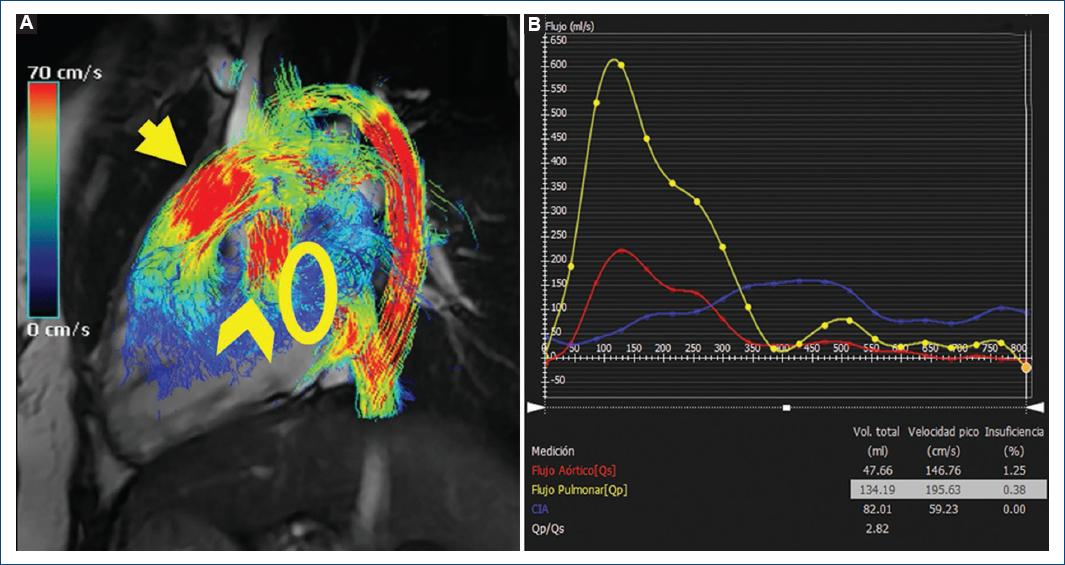

En el ejemplo 2, la cirugía de conexión cavopulmonar total o cirugía de Fontan es una técnica quirúrgica empleada como tratamiento en pacientes con cardiopatías congénitas con fisiología univentricular, entre ellas la atresia tricuspídea y la hipoplasia de cavidades izquierdas11. Esta técnica consiste en la derivación del flujo venoso sistémico a los pulmones sin pasar por las cavidades cardiacas derechas, mediante la conexión de la vena cava superior y la vena cava inferior con la arteria pulmonar12. Las complicaciones derivadas de esta cirugía se producen principalmente por la reducción del gasto cardiaco y el incremento de la presión venosa central. Dentro de ellas destacan la estenosis o trombosis del conducto Fontan, el TEP, entre otras13. Es fundamental poder analizar correctamente el circuito de Fontan y las complicaciones derivadas, como la presencia de flujo colateral. Algunos estudios indican que la presencia de flujo colateral puede influir significativamente en el estado clínico de los pacientes con fisiología de ventrículo único, ya que el flujo colateral pulmonar sistémico genera una carga de volumen en la vena pulmonar periférica, lo que puede provocar dilatación y disfunción ventricular, regurgitación de la válvula auriculoventricular y síntomas de insuficiencia cardiaca14. El flujo colateral pulmonar sistémico se calcula del siguiente modo: (flujo de las venas pulmonares izquierdas + flujo de las venas pulmonares derechas) − (flujo de la arteria pulmonar derecha + flujo de la arteria pulmonar izquierda); todos ellos evaluados mediante una secuencia activada por gatilleo electrocardiográfico con mapeo de velocidad de eco de gradiente15.

En este caso se realizó una reconstrucción en secuencia de flujo 4D coronal fusionada de la conexión cavopulmonar total y en secuencia de flujo 4D en respiración libre (Fig. 3), cubriendo el área de interés entre el túnel de Fontan (por encima de la entrada de las venas hepáticas), la vena cava superior (por debajo de la vena braquiocefálica) y las arterias pulmonares derecha e izquierda hasta los niveles de las ramas segmentarias, permitiéndonos evaluar la permeabilidad del tubo de Fontan y calcular el Qp/Qs (Fig. 4), donde se determinó la permeabilidad del mismo y la ausencia de circulación colateral aortopulmonar.